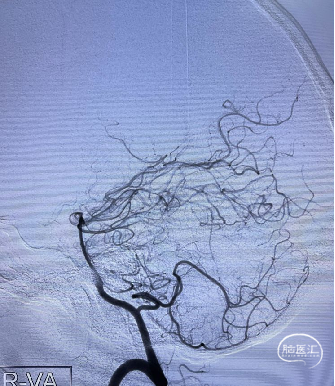

DSA:左侧大脑前动脉A2-A3动脉瘤(分叶状)

![]() 后循环造影